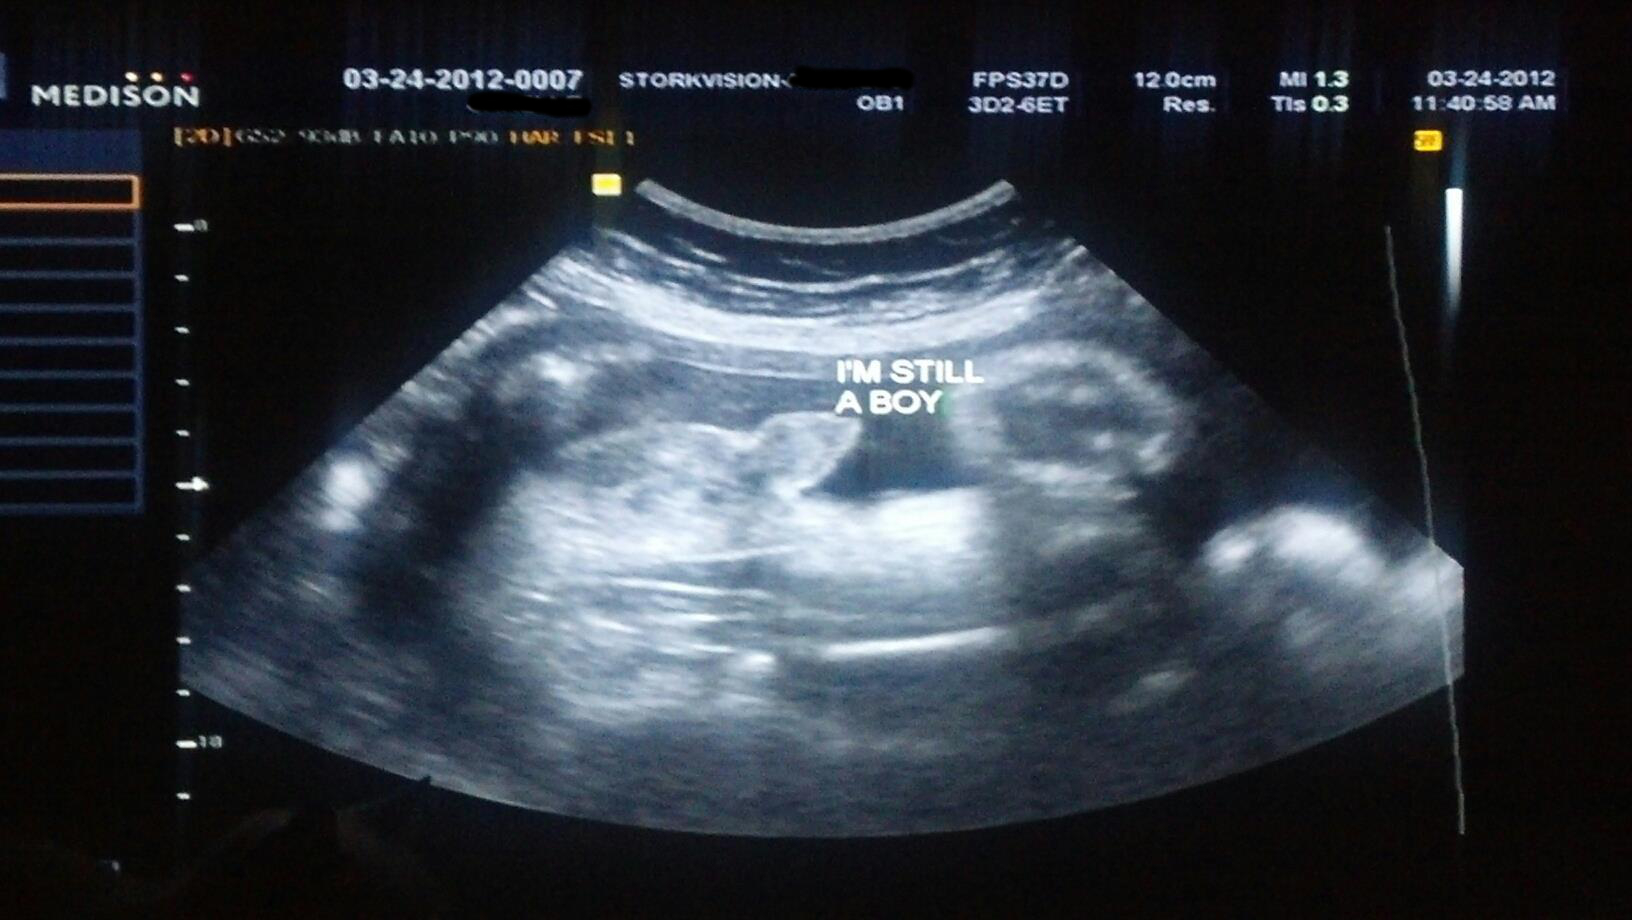

These are at 16 weeks the tech was sure 100% girl , I posted them on in gender and most people saying boy one woman in particular being very insensitive telling me to go get a refund and congratulations on my son outlining a penis on my picture. I already have 2 boys and this is my last I really was over the moon I was getting a girl now I'm so confused my 20 week scan at the hospital isn't till 11th July I don't think I can wait that long x here's the pics thank you xAttachment 19329Attachment 19330